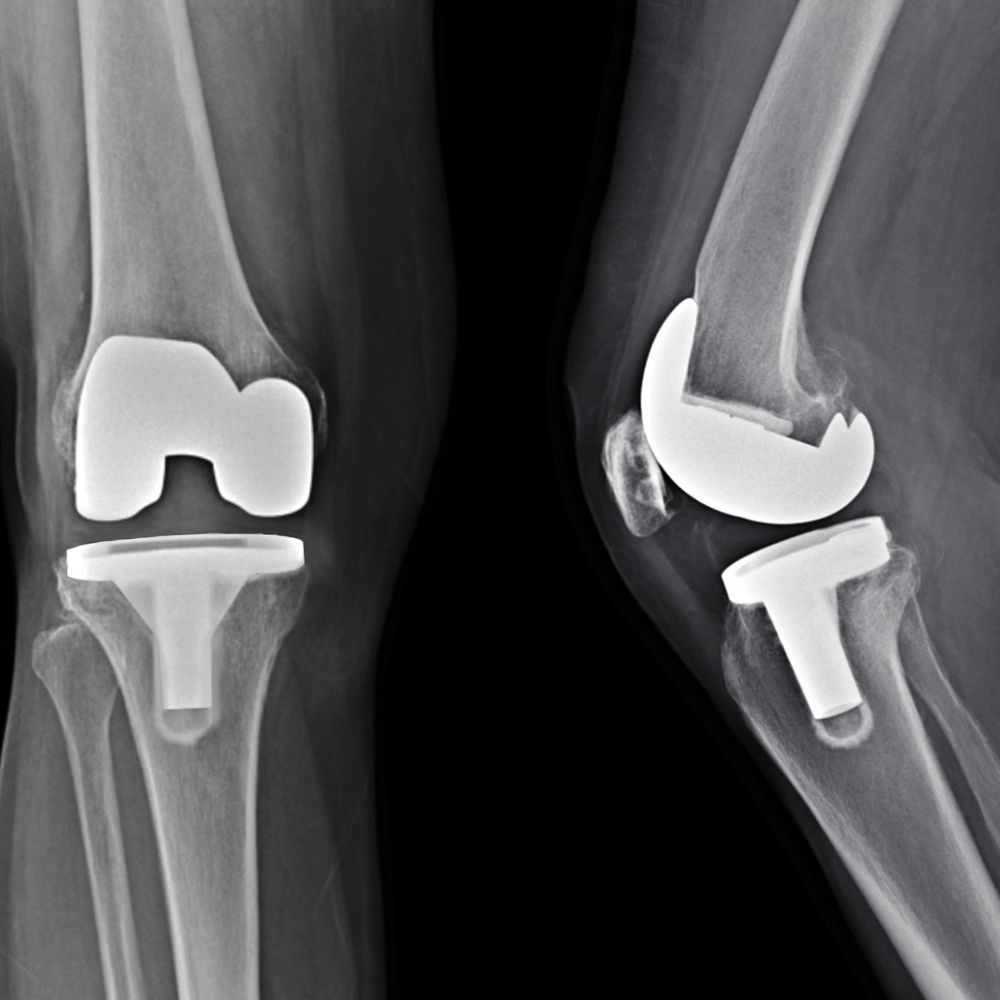

CHIRURGIA PROTESICA

Quando le terapie conservative non sono più efficaci, nei casi di artrosi molto avanzata, in cui l’articolazione è irrimediabilmente danneggiata, si rende necessario il ricorso a un intervento di chirurgia protesica, per alleviare il dolore e ripristinare la mobilità del ginocchio consentendo al paziente di tornare a condurre una vita normale, senza particolari limitazioni.

I progressi della ricerca nel campo della chirurgia protesica hanno permesso di sviluppare protesi più durature e di perfezionare le tecniche chirurgiche, rendendo gli interventi sempre meno invasivi.

Per garantire un trattamento personalizzato, seleziono la tipologia di impianto protesico più adatta a ciascun paziente, in base al suo stato di salute, alla sua età e alle sue esigenze funzionali.

Protesi totale

Per lesioni della cartilagine articolare più estese, che compromettono fortemente la qualità di vita del paziente, è necessario il ricorso all’impianto di una protesi completa.

La protesi totale di ginocchio è una soluzione che prevede la sostituzione completa dell’articolazione danneggiata, al fine di ripristinarne la funzionalità.